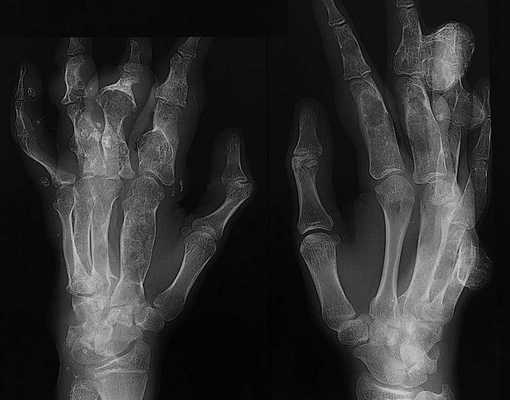

Первым признаком синдрома Маффуччи обычно является нахождение энхондромы в длинной кости (см. фото). Энхондромы искажают и ослабляют пораженные кости, поэтому первичное проявление с патологическим переломом является распространенным явлением. Эти хрящевые опухоли вызывают выпуклость костей, изгибание рук и ног и часто их непропорциональный (асимметричный) рост (разная длина рук или ног). Пациент может иметь низкий рост в зрелом возрасте. Энхондромы поражают только одну сторону тела примерно у 40 процентов пациентов.

Чтобы выявить какие-либо внутренние нарушения при синдроме Маффуччи рекомендуется провести рентгенологическое исследование, желательного всего тела. Большое внимание в данной ситуации уделяется тем участкам, где наблюдается выпячивание тканей, изменения и укорочение конечностей. Рентгенологическая симптоматика состоит из признаков хондродисплазии разной степени тяжести.

На снимках специалист может отметить ассиметричное поражение, которое характеризуется утолщением укороченных и деформированных костей трубчатого типа. При этом заметны эксцентричные просветления. Такое нарушение очень часто диагностируется в тазовой области, на лопатках, ребрах. По мере роста ребенка наблюдаются в трубчатых костях, где есть утолщения и искривления, просветления округлой формы, могут присутствовать энхондромы.

Также при синдроме Маффуччи фото рентгена может показывать различные тени флеболитов, имеющих диаметр не более 0,4 см. Их легко заметить. Они гомогенные и обладают четким очертанием.